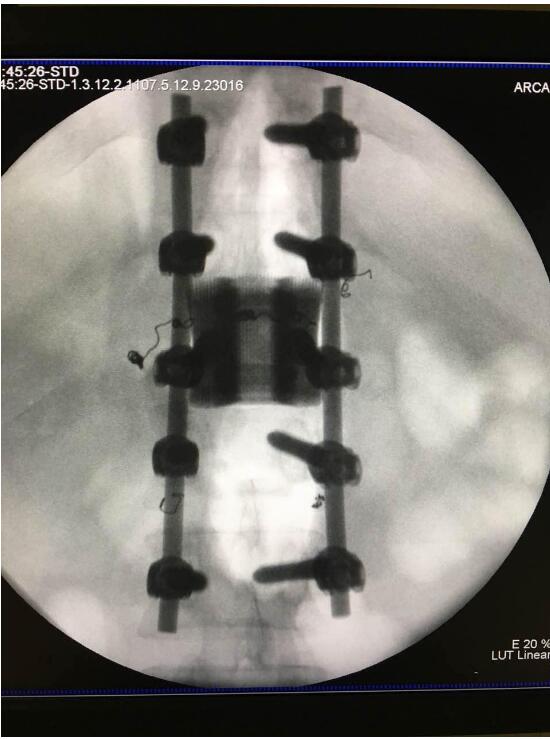

2018年2月7日華鈦三維與南方醫(yī)院脊柱骨外科聯(lián)合澳大利亞技術(shù)科學(xué)與工程院吳鑫華院士領(lǐng)導(dǎo)的莫納什大學(xué)增材制造研究中心合作的世界第一例3D打印個(gè)性化“人工椎體/椎間盤一體化“植入手術(shù)成功實(shí)施。不僅保住了病人的脊椎,還保住了其日后的活動(dòng)能力。

這次手術(shù)是廣州華鈦三維骨科研究中心(華鈦三維骨科研究院)與南方醫(yī)院聯(lián)合澳大利亞技術(shù)科學(xué)與工程院吳鑫華院士領(lǐng)導(dǎo)的莫納什大學(xué)增材制造研究中心合作的世界第一例3D打印個(gè)性化人工椎體/腰間盤一體化植入手術(shù)。南方醫(yī)院脊椎及骨病外科鄭明輝副主任醫(yī)師在嶺南名醫(yī)陳建庭主任和朱青安教授指導(dǎo)下,與華鈦三維工程師陸國(guó)贊合作構(gòu)思設(shè)計(jì),澳大利亞莫納什大學(xué)增材制造研究中心主任吳鑫華院士團(tuán)隊(duì)進(jìn)行了一個(gè)多月的個(gè)性化鈦合金3D打印工藝研究,成功打印出符合病人要求的人工椎體/腰間盤一體化植入物。這次手術(shù)的成功,標(biāo)志著中國(guó)的3D打印植入物技術(shù)在骨科醫(yī)療領(lǐng)域達(dá)到世界先進(jìn)水平。

為了更好的完成手術(shù),陳建庭主任、鄭明輝副主任醫(yī)師等骨科專家與華鈦三維的3D打印專家從2017年10月份開始籌備該手術(shù)??紤]到每一個(gè)病人的脊椎形狀都存在差異,骨科專家認(rèn)為用一個(gè)現(xiàn)成的標(biāo)準(zhǔn)植入物不大可能匹配病人的生理參數(shù)。醫(yī)學(xué)專家和3D打印專家根據(jù)病人脊柱的CT掃描數(shù)據(jù),為病人的脊柱建立了精準(zhǔn)的3D圖像。根據(jù)這個(gè)圖像,治療團(tuán)隊(duì)就能夠設(shè)計(jì)并定制出屬于病人的個(gè)性化植入物。為了使個(gè)性化定制的人工椎體與病人椎體之間更好的融合,手術(shù)實(shí)施前治療團(tuán)隊(duì)先后設(shè)計(jì)了100多個(gè)方案,制作了數(shù)十個(gè)植入物的術(shù)前模型進(jìn)行研討。事實(shí)證明,手術(shù)最終使用的植入物是最適合手術(shù)和病人身體情況的。

利用3D打印技術(shù)生產(chǎn)出來的人工椎體是完全按照患者的解剖結(jié)構(gòu)完成脊椎結(jié)構(gòu)重建及固定的, 裝上一枚精準(zhǔn)的、個(gè)性化的人工脊椎,患者康復(fù)后完全可以正常地生活和工作。過去這種手術(shù)常常是使用鈦網(wǎng)內(nèi)填入自體或異體碎骨作為椎體間支撐材料,但鈦網(wǎng)一旦移位壓迫脊髓,患者就會(huì)有癱瘓的風(fēng)險(xiǎn)。這次手術(shù)中的脊椎植入物內(nèi)部具有經(jīng)過力學(xué)優(yōu)化設(shè)計(jì)的晶格結(jié)構(gòu),比傳統(tǒng)鈦網(wǎng)具有更強(qiáng)的承重力,金屬3D打印可以直接制造出這樣的復(fù)雜結(jié)構(gòu)。

最終在經(jīng)歷近八個(gè)小時(shí)后,病人的家屬終于等到了好消息:人工椎體/椎間盤一體化金屬植入物成功植入,手術(shù)順利。由于病人術(shù)中出血量小,生命體征平穩(wěn),他不用進(jìn)入ICU觀察,直接回到了普通病房。“現(xiàn)在我們都很高興,成功做出了世界首例人工椎體/椎間盤一體化金屬植入物,病人今后可以與常人一樣工作和生活。”鄭明輝醫(yī)生說。